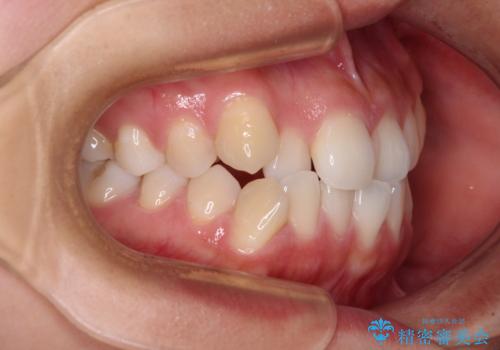

- 前歯のデコボコを治したいとのことで来院された患者様です。

インビザラインによるマウスピース矯正も適用となる歯列でしたが、できる限り楽して、短期間で治したいとのことで、ワイヤー装置にて矯正治療を行うこととしました。